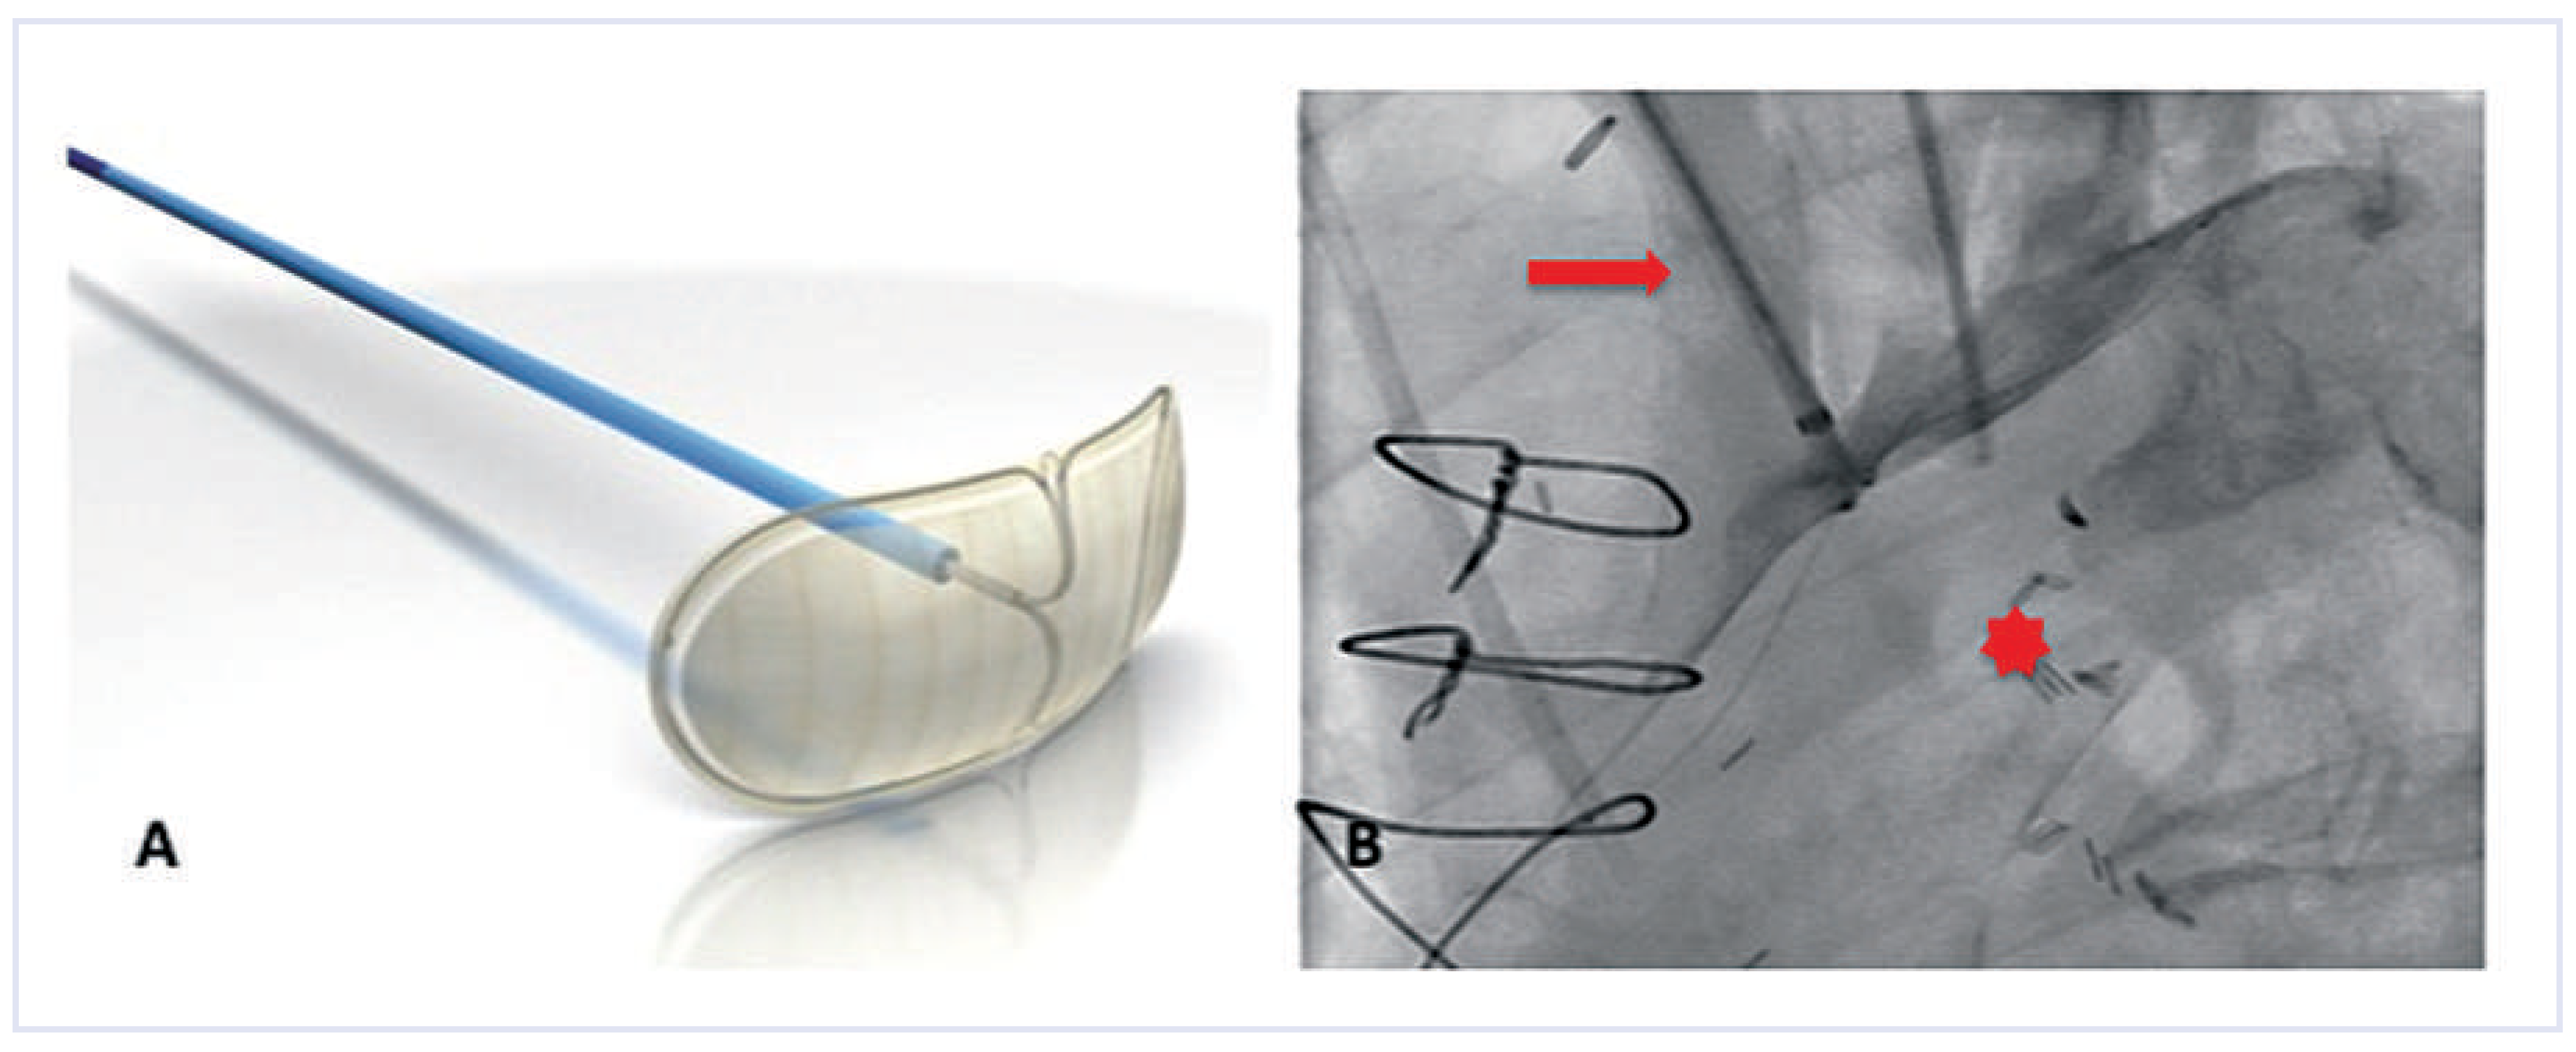

Figure 1. The Embrella device. (A)The device consists of two petals and a delivery cable. (Courtesy of Edwards Lifesciences Ltd., Irvine, CA, USA.). (B) Once positioned at the outer curvature of the aortic arch, a contrast injection through the delivery sheath confirms proper placement. Note that the two petals of the device cover the brachiocephalic trunk and the left carotid artery. Red arrow = brachiocephalic trunk; red star = aortic lumen.

The Embrella device (Edwards Lifesciences Ltd., Irvine, CA, USA) is introduced either through the right radial or brachial artery. The concept of the device is to deflect rather than to capture emboli. Proof-of-concept was shown in the year 2010 in a first-in-human study [16]. The study confirmed the simple handling of the device, with an additional procedural time of only 13 minutes. Whether it is an atraumatic and effective device needs further investigation in a large trial. The Embrella is an umbrella-like device that consists of 2 polyurethane membranes mounted on a nitinol frame. The device is attached to a 0.035-inch nitinol delivery cable (Figure 1A). It can be folded, sheathed and loaded into a 6F long delivery sheath, which itself is placed over the right radial or brachial artery into the ascending aorta. Then the device consisting of two petals is released from the sheath. It is pulled back and positioned at the outer curvature of the aortic arch such that the petals cover the left carotid and the innominate artery (Figure 1B). In some patients it will further (partially) cover the left subclavian artery. The polyurethane membrane has 100-µm pores to ensure proper blood circulation downstream of the device.

Sitting at the outer curvature of the aortic arch, the device does not interfere with the TAVI procedures, and in particular there is no interference with the large valve delivery system. Once the procedure is terminated, the device is re-sheathed using the 6F delivery sheath.